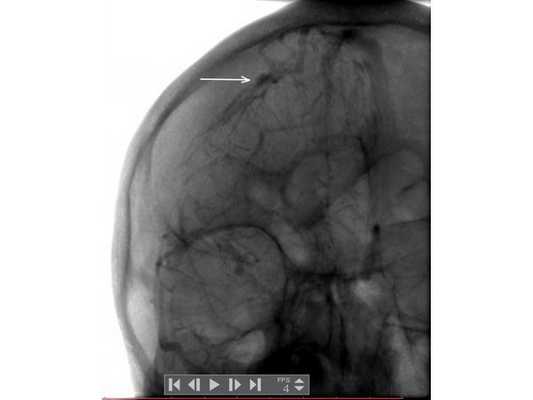

Анализ крови на алкоголь — 0 промилле. Выполнена диагностическая люмбальная пункция, выявлено субарахноидальное кровоизлияние: 10-15 эритроцитов в поле зрения. При помощи эхоэнцефалоскопии обнаружено смещение срединных структур головного мозга на 3-4 мм влево. Т.е. у пациента имеются клинические данные, указывающие на внутричерепную гематому справа, но при отсутствии КТ/МРТ-диагностики определить её объём и локализацию сложно. Для дальнейшего диагностического поиска пациенту выполнена церебральная ангиография. На ангиограммах отмечено отжатие сосудистой сети правого полушария головного мозга от костей свода черепа почти на 10 мм (рис. 1). В левом полушарии патологии не выявлено (рис. 2).

Пациент взят на операцию: ⠀•⠀Выполнен дугообразный разрез мягких тканей в правой лобно-височно-теменной области. Скелетирована кость. ⠀•⠀Наложены два фрезевых отверстия, из которых краниотомом выпилен костный лоскут 6,0*8,0 см. ⠀•⠀Произведён гемостаз моно- и биполярной коагуляцией, воском по ходу доступа. ⠀•⠀Твёрдая мозговая оболочка вскрыта подковообразно. Визуализирована субдуральная гематома, представленная плотными сгустками тёмно-вишнёвого цвета (рис. 3). ⠀•⠀Начато удаление сгустков путём аспирации и отмыванием физиологическим раствором. Общий объём субдуральной гематомы около 120 мл. Признаков черепно-мозговой травмы (кортикальных очагов ушиба, травматического субарахноидального кровоизлияния, гиперемии, отёка головного мозга) нет. ⠀•⠀При удалении сгустков с конвекситальной поверхности лобной доли открылось интенсивное венозное кровотечение. С целью доступа к источнику кровотечения разрез мягких тканей продолжен в конвекситальном направлении и краниотомом выпилены два дополнительных костных лоскута (из-за интенсивности кровотечения найти локализацию источника было затруднительно). ⠀•⠀Визуализировано кровоточащее образование, сращённое с твёрдой мозговой оболочкой и корой головного мозга, по виду — сосудистая мальформация (рис. 4). ⠀•⠀Гемостаз подходящих сосудов и самого образования выполнен последовательной биполярной коагуляцией (рис. 5: сосудистая мальформация указана наконечником аспиратора). ⠀•⠀Кровотечение остановлено. Мозг расправился, пульсирует. Твёрдая мозговая оболочка ушита викрилом с одновременным подшиванием по периметру трепанационного окна (рис. 6). ⠀•⠀Дефекты твёрдой мозговой оболочки и сосудистая мальформация укрыты гемостатической губкой (рис. 7). ⠀•⠀Костные лоскуты уложены на место (рис. 8). ⠀•⠀Послойный шов раны выполнен викрилом и капроном. ⠀•⠀Кожа ушита обвивным швом по Мультановскому. Ретроспективно на фронтальной ангиограмме можно заподозрить сосудистую мальформацию, ставшую источником гематомы (рис. 9). На девятые сутки после операции для обеспечения проходимости дыхательных путей, проведения длительной искусственной вентиляции лёгких, облегчения санации трахеи и бронхов пациенту выполнена нижняя трахеостомия по Бьёрку.

Данный клинический случай показывает, что при отсутствии КТ/МРТ ангиографическое исследование позволяет локализовать внутричерепную гематому и приблизительно оценить её объём. Источник гематомы верифицирован также благодаря этому виду обследования. Если почитать старые руководства по нейрохирургии 70-80-х годов прошлого века, можно убедиться, что церебральная ангиография очень часто применялась для диагностики гематом головного мозга, опухолей, не говоря уже о сосудистой патологии.